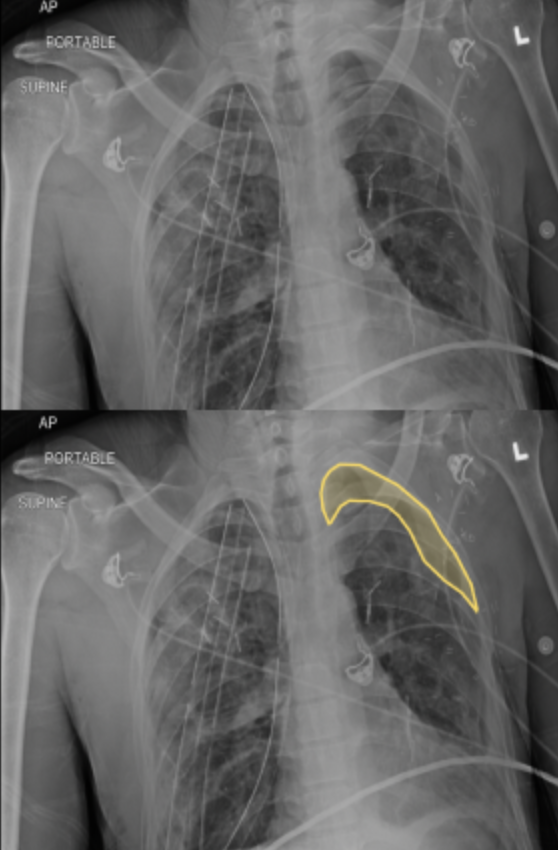

A pneumothorax is colloquially referred to as a "collapsed lung." Pneumothorax is created when the visceral and parietal pleura of a lung š« are no longer are attached. Trauma, blebs (when there's too much coughing for example) or other injuries can all result in pneumothoraces. In this contest, you will be tracing pneumothoraces.

A pneumothorax is air that fills the newly created space between the visceral and parietal pleura. Look for the lack of lung lining or darker areas to make your annotation.